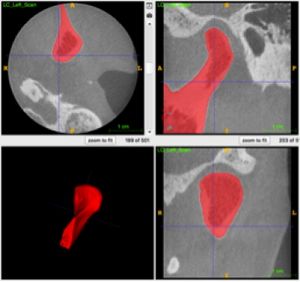

Diffusion Weighted And Dynamic Contrast Enhanced MRI as an Imaging Biomarker for Stereotactic Ablative Body Radiotherapy (SABR) of Primary Renal Cell Carcinoma

Publication: PLoS One. 2018 Aug 16;13(8):e0202387. PMID: 30114235 | PDF Authors: Reynolds HM, Parameswaran BK, Finnegan ME, Roettger D, Lau E, Kron T, Shaw M, Chander S, Siva S. Institution: Department of Physical Sciences, Peter MacCallum Cancer Centre, Melbourne, Victoria, Australia. Abstract: PURPOSE: To explore the utility of diffusion and perfusion changes in primary renal cell carcinoma (RCC) after stereotactic ablative body radiotherapy (SABR) as an early biomarker of treatment response, using diffusion weighted (DWI) and dynamic contrast enhanced (DCE) MRI. METHODS: Patients enrolled in a prospective pilot clinical trial received SABR for primary RCC, and had DWI and DCE MRI scheduled at baseline, 14 days and 70 days after SABR. Tumours <5cm diameter received a single fraction of 26 Gy and larger tumours received three fractions of 14 Gy. Apparent diffusion coefficient (ADC) maps were computed from DWI data and parametric and pharmacokinetic maps were fitted to the DCE data. Tumour volumes were contoured and statistics extracted. Spearman's rank correlation coefficients were computed between MRI parameter changes versus the percentage tumour volume change from CT at 6, 12 and 24 months and the last follow-up relative to baseline CT. RESULTS: Twelve patients were eligible for DWI analysis, and a subset of ten patients for DCE MRI analysis. DCE MRI from the second follow-up MRI scan showed correlations between the change in percentage voxels with washout contrast enhancement behaviour and the change in tumour volume (ρ = 0.84, p = 0.004 at 12 month CT, ρ = 0.81, p = 0.02 at 24 month CT, and ρ = 0.89, p = 0.001 at last follow-up CT). The change in mean initial rate of enhancement and mean Ktrans at the second follow-up MRI scan were positively correlated with percent tumour volume change at the 12 month CT onwards (ρ = 0.65, p = 0.05 and ρ = 0.66, p = 0.04 at 12 month CT respectively). Changes in ADC kurtosis from histogram analysis at the first follow-up MRI scan also showed positive correlations with the percentage tumour volume change (ρ = 0.66, p = 0.02 at 12 month CT, ρ = 0.69, p = 0.02 at last follow-up CT), but these results are possibly confounded by inflammation. CONCLUSION: DWI and DCE MRI parameters show potential as early response biomarkers after SABR for primary RCC. Further prospective validation using larger patient cohorts is warranted. |

Baseline ADC map with tumour contour in red for patient 3 and associated histogram showing the frequency of ADC values in each MRI scan. ADC maps were read into 3D Slicer software and the tumour volume contoured directly onto ADC map image slices by an experienced radiologist. |